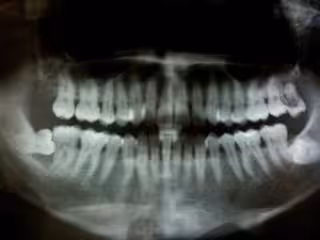

Periodontitis

Periodontitis - FLICKR/FELIX E. GUERRERO - Archivo